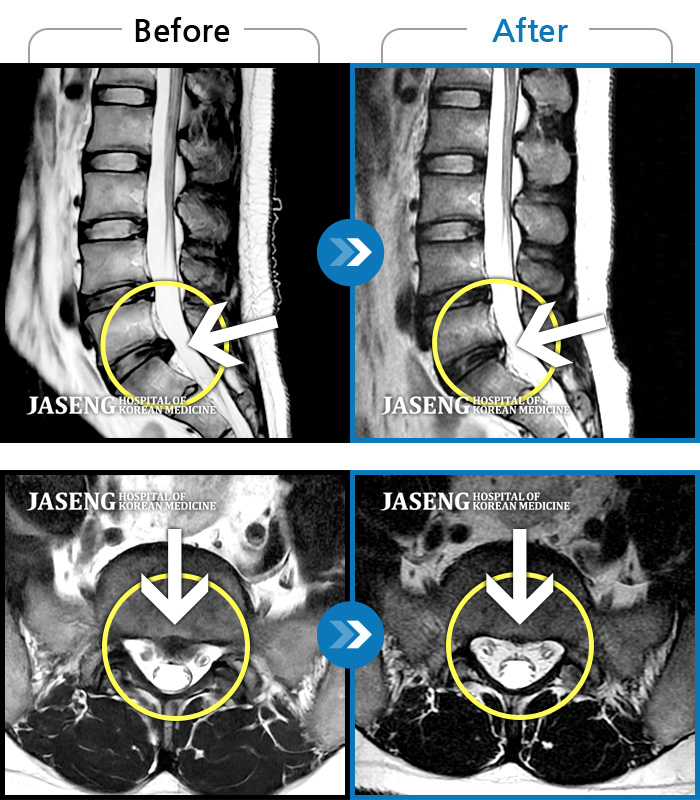

운동 중 급격하게 발생한 후경부~좌측 어깨 및 좌측 상지 전반적인 저림이 있었다.

2021.10.26 ~ 2023.12.16